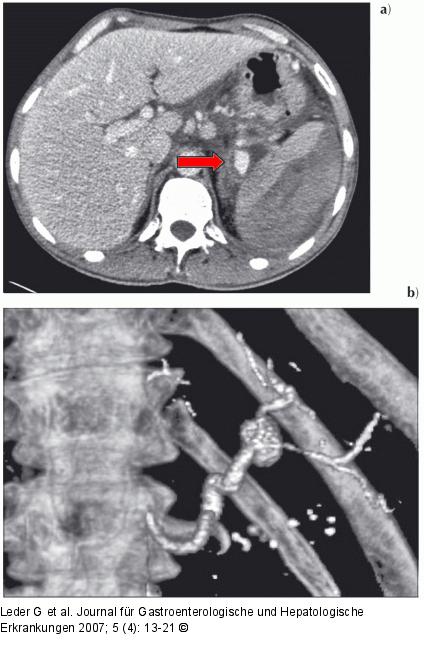

Abbildung 7: Chronische Pankreatitis a) Die Milz ist durch ein geschichtetes, subkapsuläres, ventral rupturiertes Hämatom massiv vergrößert (CT 20.1. 2007, venöse Phase). Gegenüber der Leber ist die Durchblutung der Milz vermindert. Das Pseudoaneurysma (→) ist größenprogredient. b) Die Gefäßrekonstruktion zeigt das Pseudoaneurysma und die distal davon nur noch dünne A. lienalis. |

a) Die Milz ist durch ein geschichtetes, subkapsuläres, ventral rupturiertes Hämatom massiv vergrößert (CT 20.1. 2007, venöse Phase). Gegenüber der Leber ist die Durchblutung der Milz vermindert. Das Pseudoaneurysma (→) ist größenprogredient. b) Die Gefäßrekonstruktion zeigt das Pseudoaneurysma und die distal davon nur noch dünne A. lienalis. |